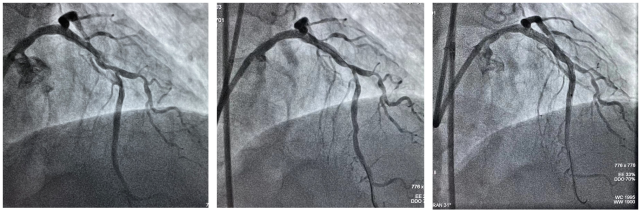

Shockwave球囊冲击波治疗冠状动脉钙化病灶前后造影及支架植入术后造影